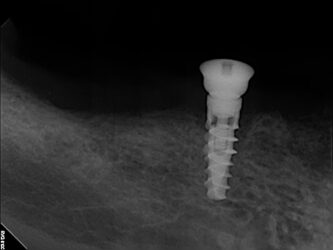

• We all can agree you want a minimum of 1.5 between implant and tooth. What are the risks if it is 1.2 or 1.0. Are they ways to still have success?

Attached is a picture of an immediate implant placement after extraction, threading the needle. In the picture we had 1.5 mm but I know posts with pictures do better lol.